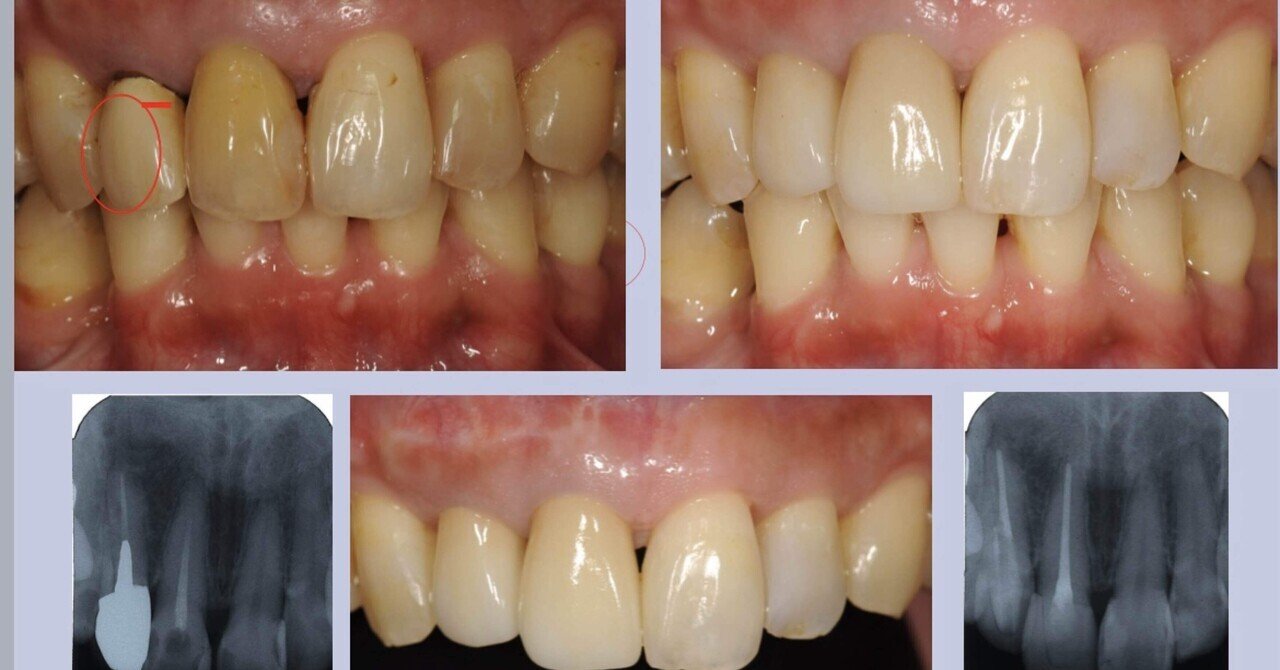

歯内療法NextStep樋状根とRadixEntomolarisへの対応

?ヒョーロン・パブリッシャーズ

辻本恭久

2023/02/21

4864320764

9784864320764